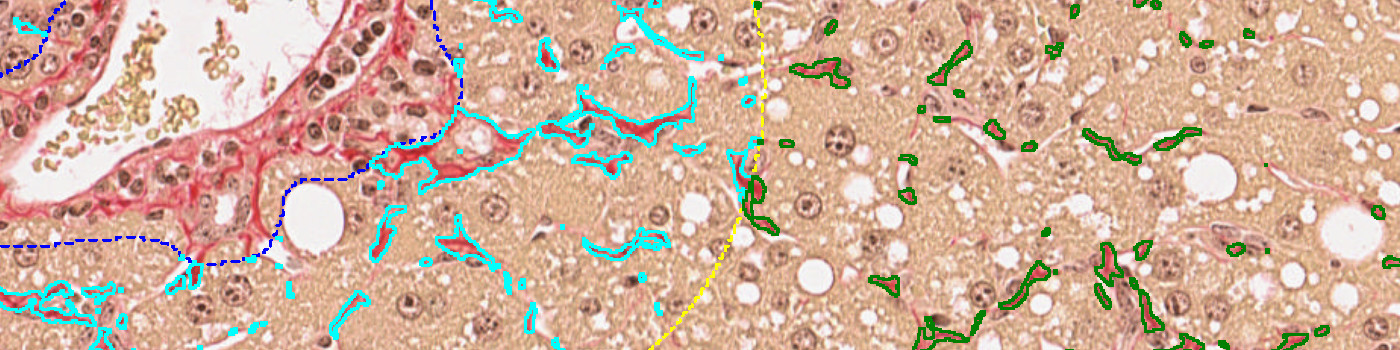

Figure 6

PSR stained liver tissue with identified fibrosis. Fibrosis in the perisinusoidal space is shown in green and the fibrosis in the periportal space is shown in turquoise.